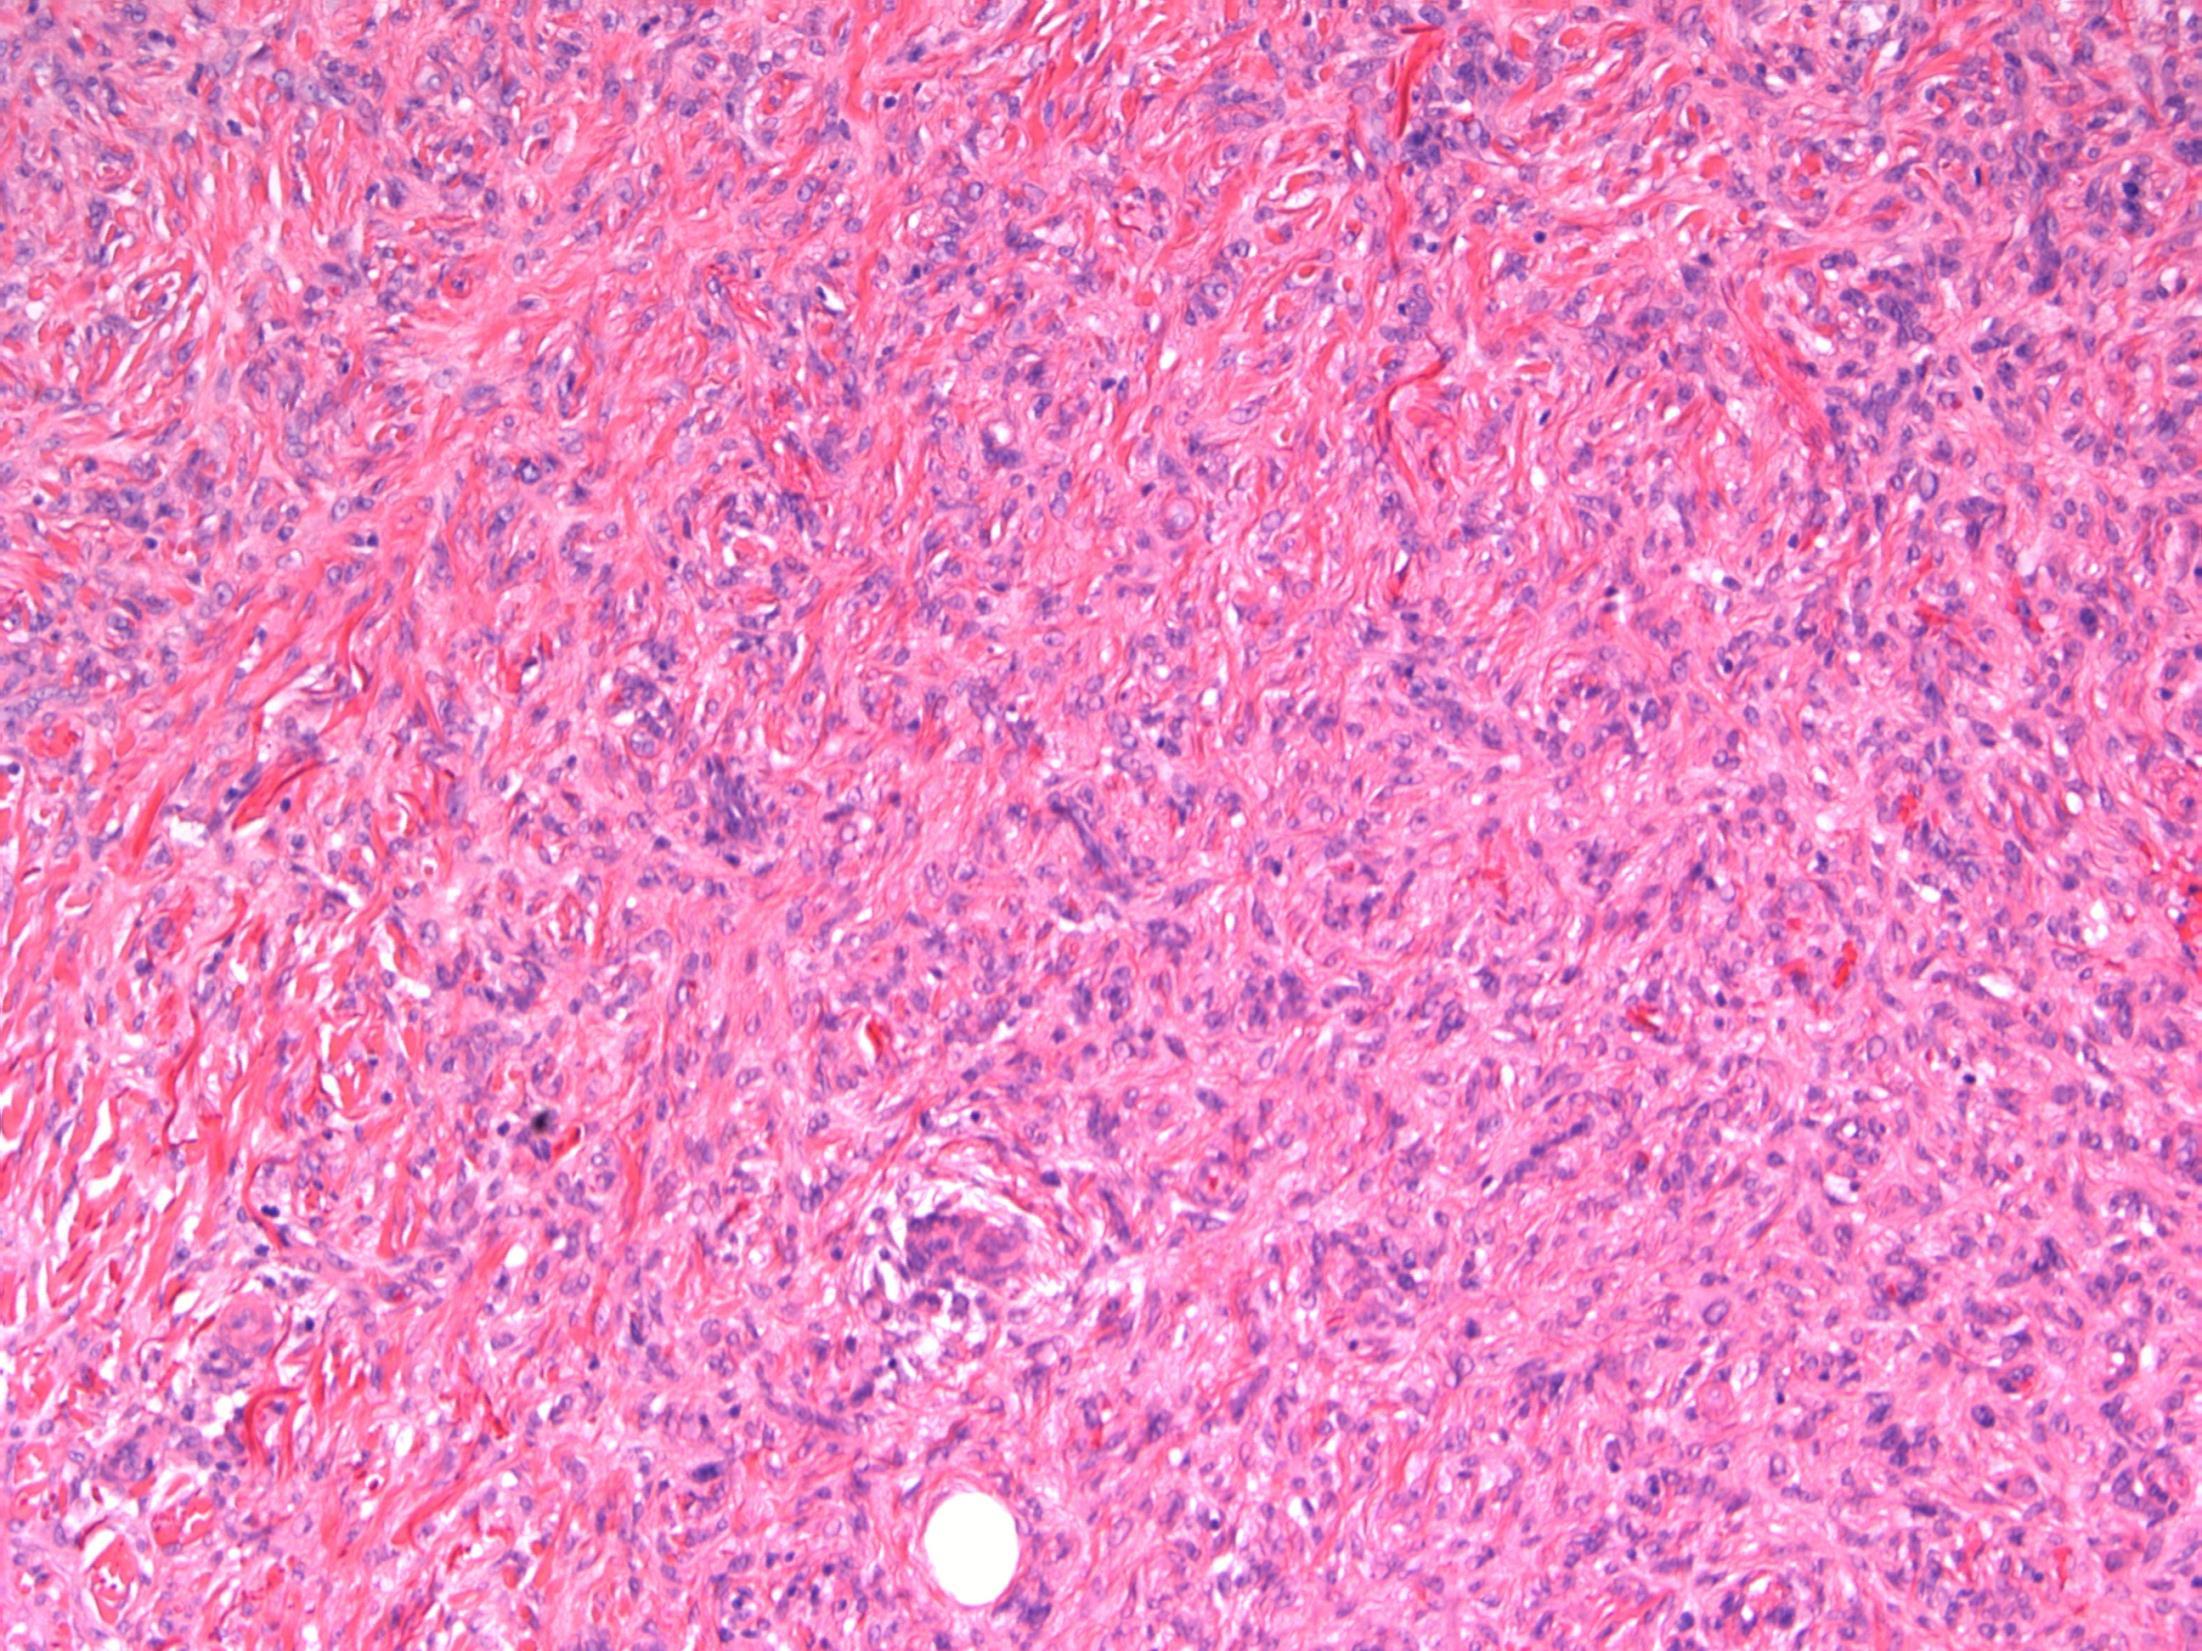

Dermatofibroma

Description: Pseudoepitheliomatous hyperplasia of the overlying epidermis. In dermis –short fascicles of spindle cells with individual collagen bundles surrounded by lesional cells at the periphery; giant cells, macrophages, inflammatory cells. Focal extension to subcutis.

Diagnosis: dermatofibroma

Plan: Correlate with clinical history: Often appear after a minor injury to the skin, vaccination or insect bite. Check other blocks for excision status.

Comments:

Many variants (aneurysmal, cellular, atypical)

Benign behaviour

Extremities commonly affected – like in this case. Local recurrence is rare, even with involved margins

3.5 Behaviour; correlation with history 3.0 Justification of diagnosis and exclude other malignant diagnosis (?IHC) 2.5 Description with diagnosis 2.0 Other benign diagnosis with mention of dermatofibroma 1.5 Other diagnosis with no mention of dermatofibroma 1.0 Malignant diagnosis